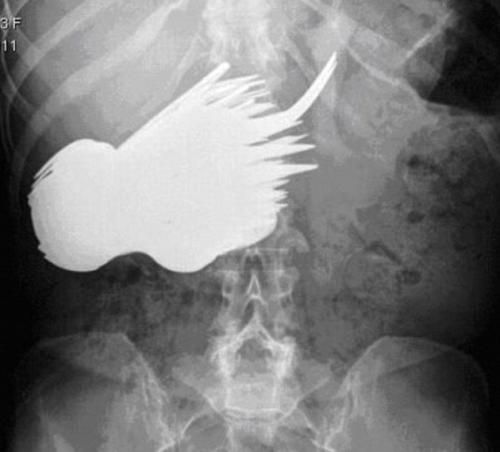

お尻は日本でもたまーに救急に来るで

肛門 異物

肛門に異物はよくあるらしい。やり過ぎると地主になってしまうので程ほどにね。

尻に異物が入る時はだいたい「転んだ拍子に」って言うけど医療関係者はそんな与太話は誰も信じてないだろうね。